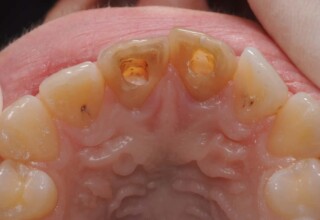

Dark root canal teeth

A rare case of dark root canal teeth with additional external absorption on the central incisor. After removal of the affected tissues of the central incisor, the tooth could not be directly bleached because of the soft tissue contact. The tooth was initially restored to provide the original tooth form, then it was bleached and the restoration was finalized.

Final appearance